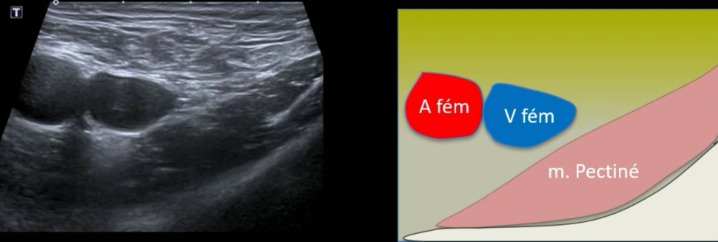

Hernie fémorale

Technique

- Permet de tester le valsalva

- Repères anatomique

- Vx fémoraux

- Muscle pectiné

crural crurale femoral

Test du valsalva

Hernie fémorale